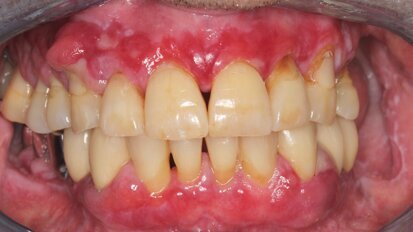

La enfermedad periodontal fuera de la cavidad bucal (1)

El Dr. Enrique Jadad aborda en este primer artículo los efectos negativos que la enfermedad periodontal puede provocar como consecuencia de su capacidad ...